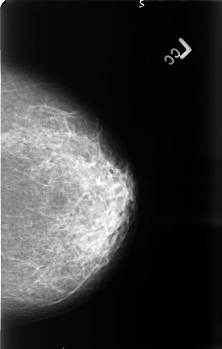

B_3399_1.LEFT_MLO

LEFT_MLO LINES 4552 PIXELS_PER_LINE 2888 BITS_PER_PIXEL 12 RESOLUTION 50 NON_OVERLAY